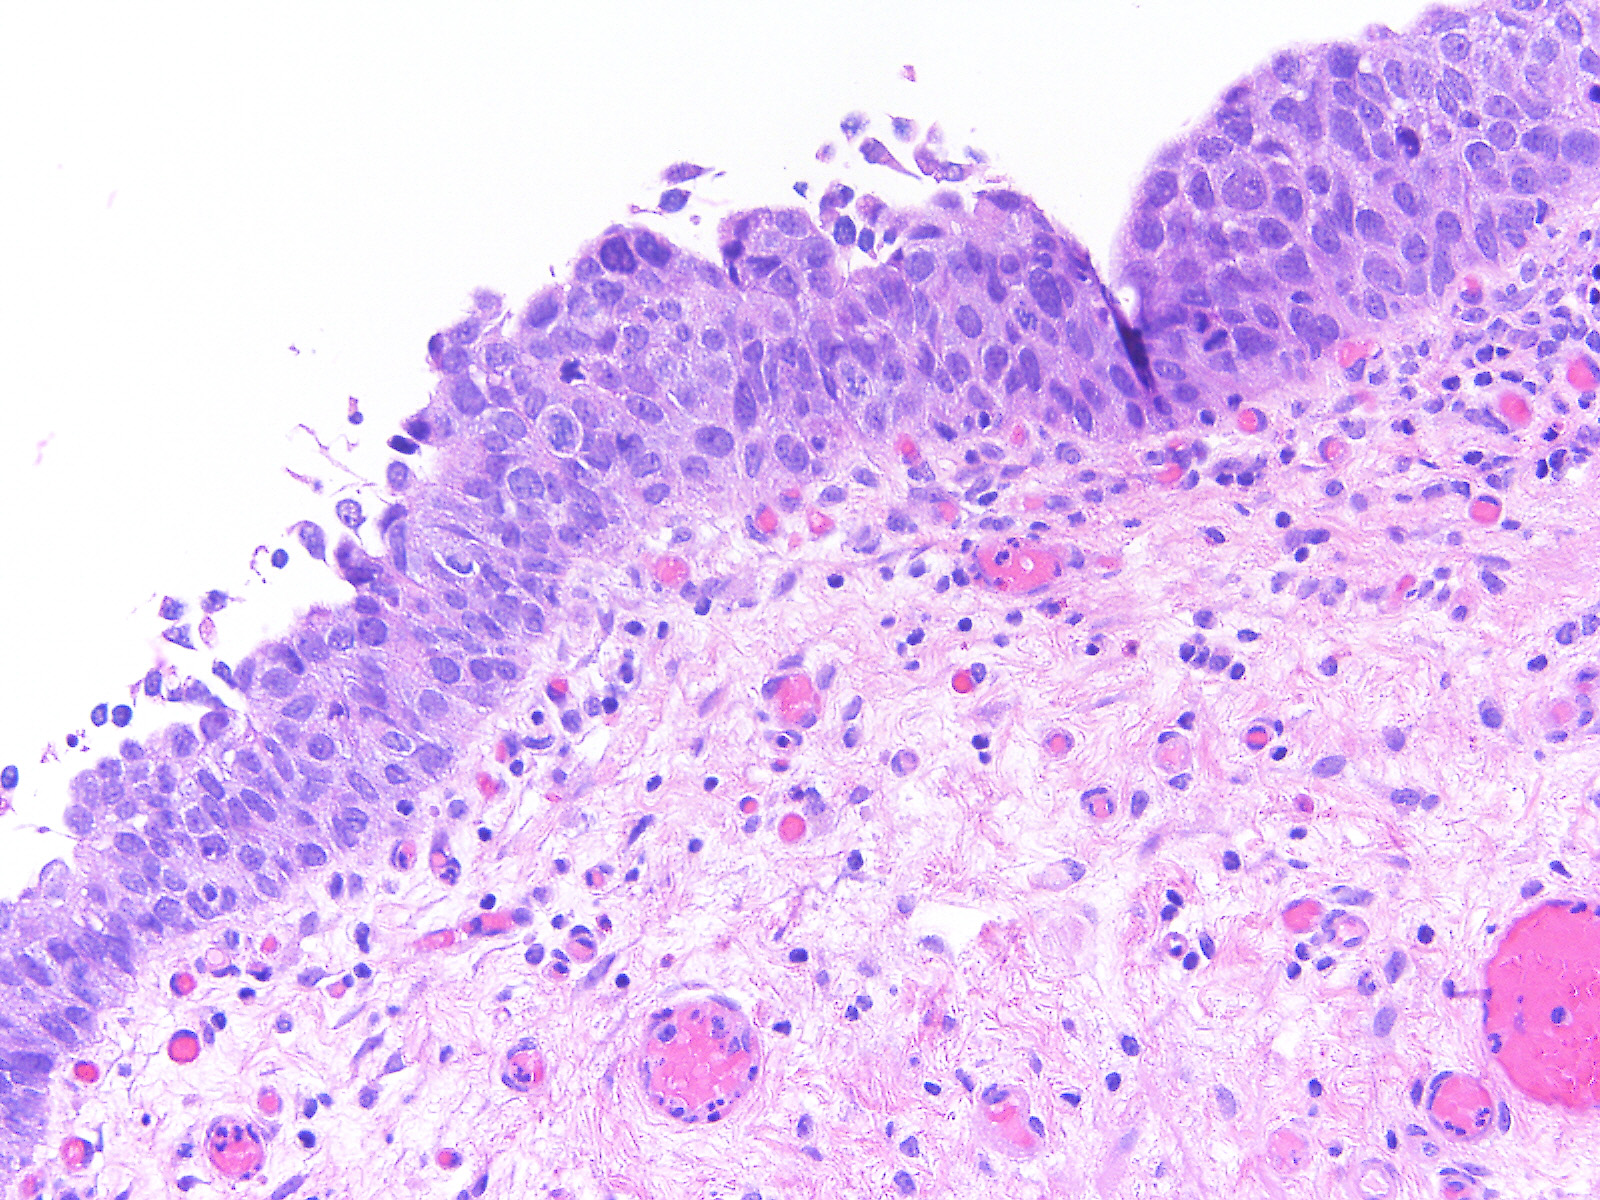

Consensus grade: Carcinoma in situ (CIS)

Case description (by case creator):

A 49-year-old man underwent a 2nd look bladder cystoscopy and TUR of a prior biopsy site.